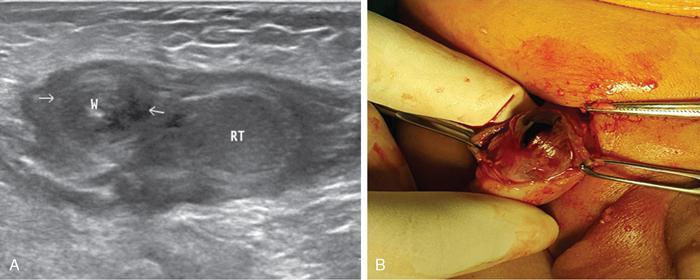

Intraabdominal testis is more prone for malignant transformation whereas canalicular testis for torsion (bulky heteroechoic testis, devoid of internal vascularity, with adjacent whirlpool sign or mass). In canalicular torsion testis the child usually presents with acute painful groin swelling (Figs. 11.8.7–11.8.8).

Fig. 11.8.8(A) Right inguinal US scan of a 9-month-old male child showing undescended hypoechoic right testis (RT) in inguinal canal with adjacent spermatic cord twist W (between arrows), s/o torsion of undescended canalicular right testis. (B) Preoperative and gross specimen photographs of the same case showing post torsion infarcted/gangrenous right testis derived from inguinal canal.